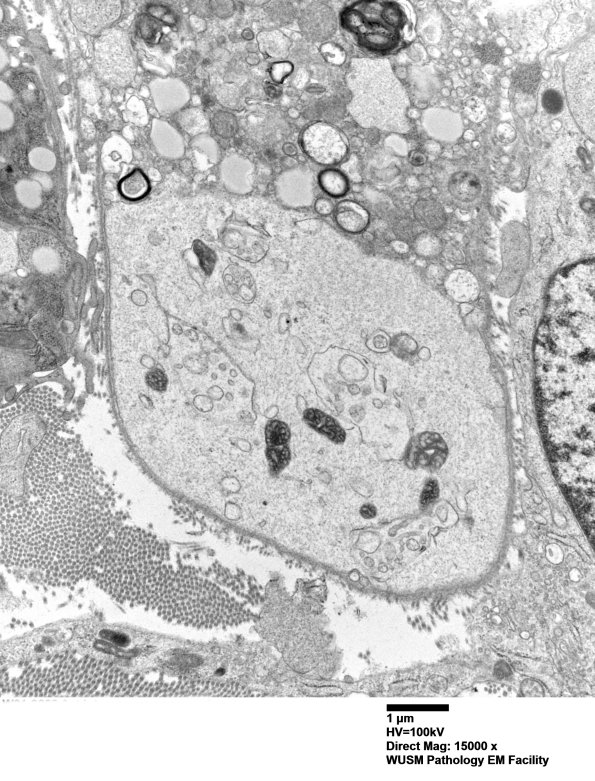

4F4B A higher magnification of image #4F4A showing a very busy structure adjacent to a macrophage containing myelin debris and lipid droplets. My first temptation in this setting and ultrastructural environment is that this is a demyelinated axon; however, it has an unusual content compared to typical demyelinated axons and I am not entirely sure. Most Schwann processes in this case are nowhere near this large. (electron micrograph)